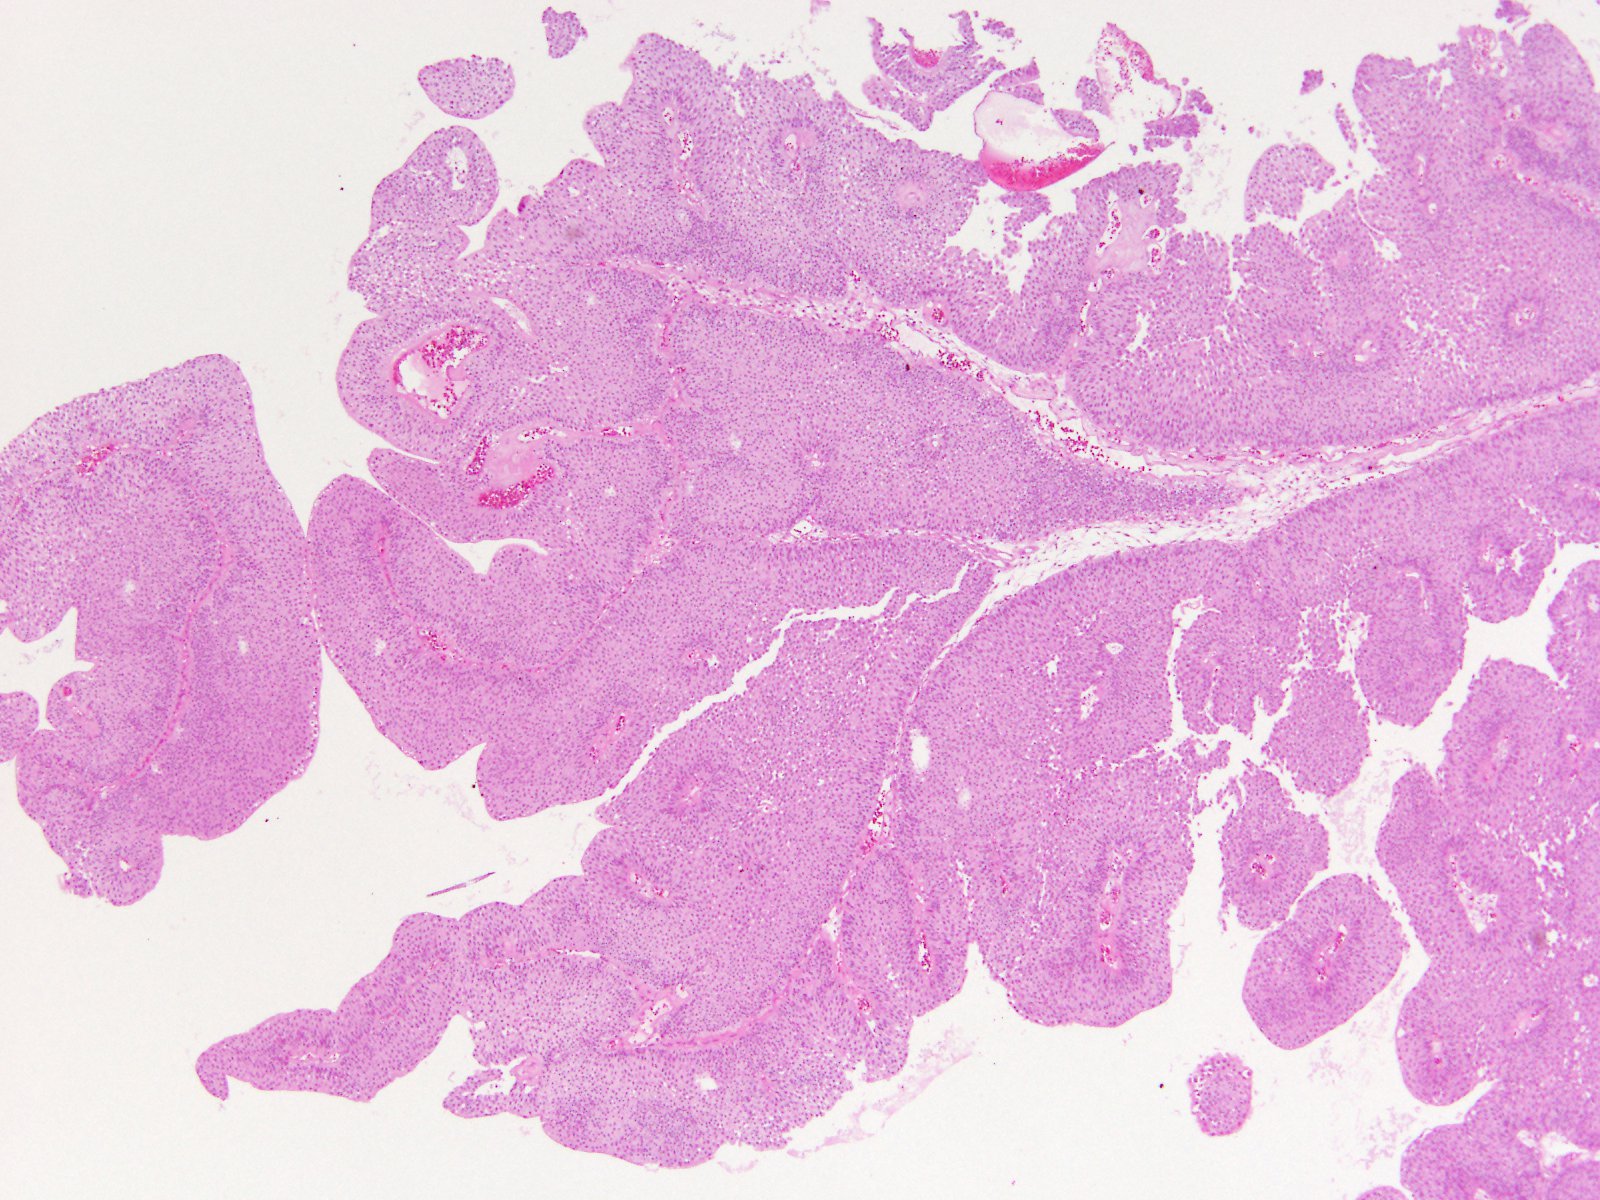

Consensus grade: Low-grade papillary urothelial carcinoma (LG-PUC)

Case description (by case creator):

71 y/o, bladder tumor.